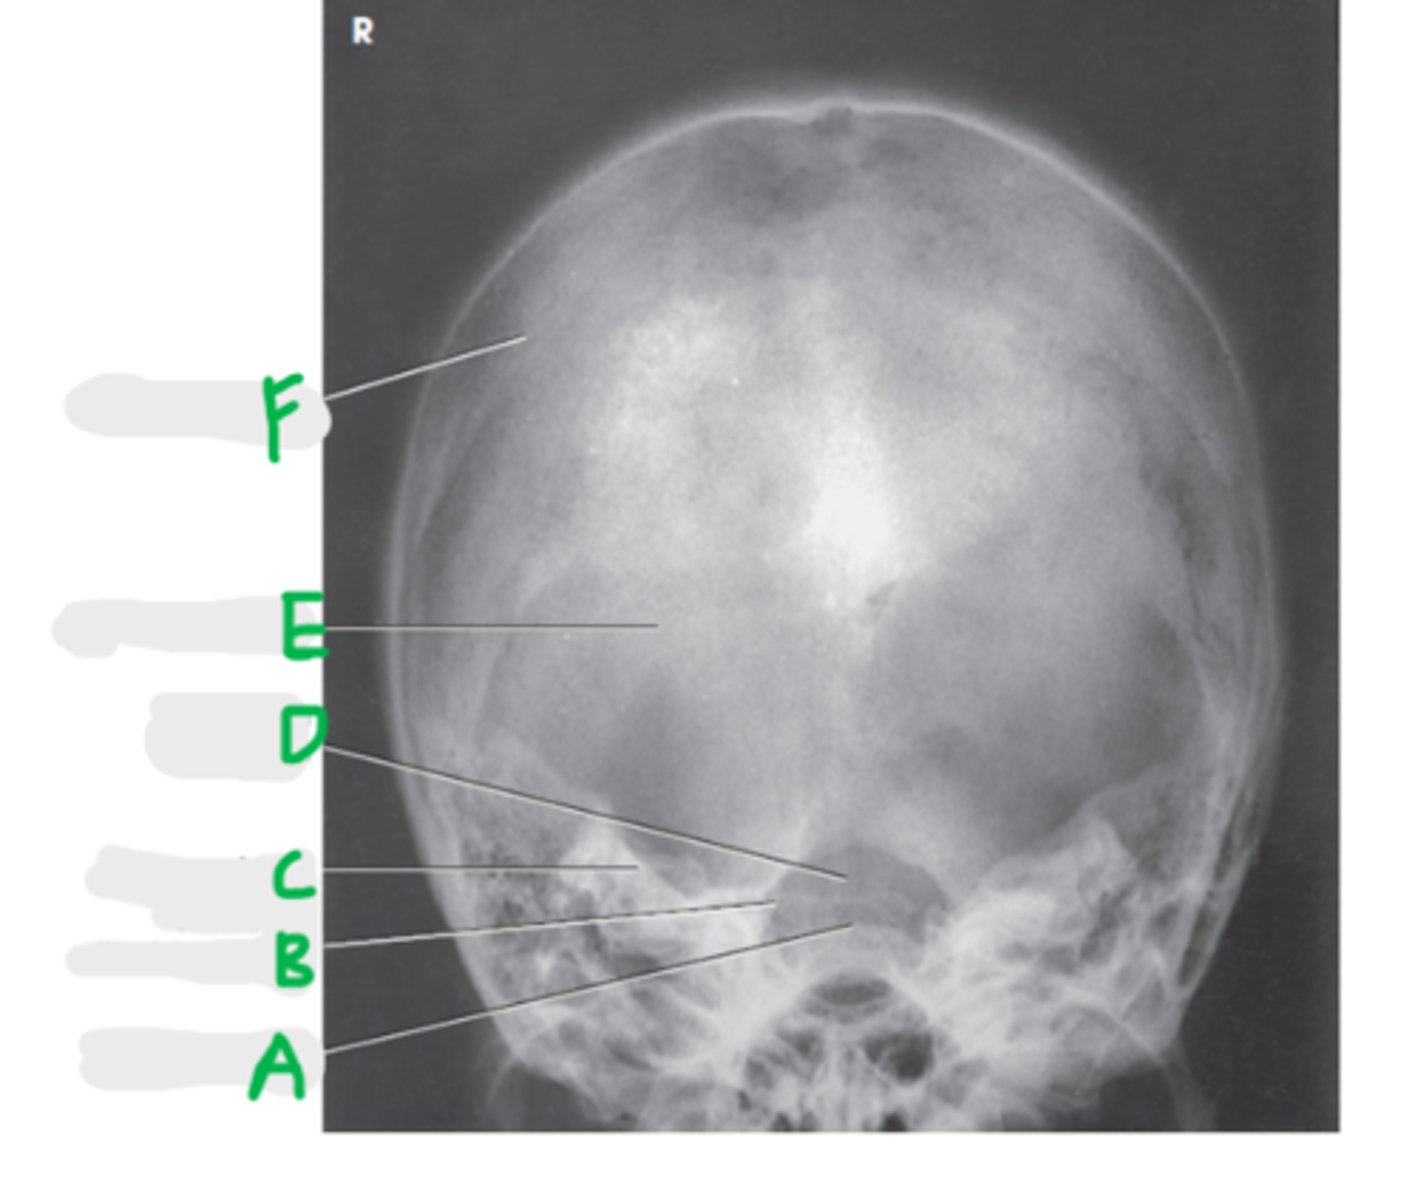

Frontal sinus

A

Crista galli

B

Superior orbital margin

C

Superior orbital fissure

D

Ethmoid sinus

E

Petrous ridge

F